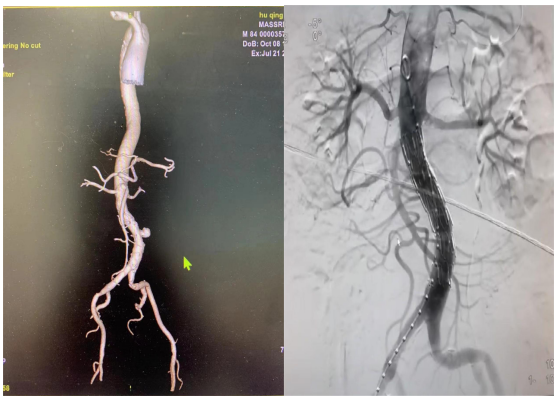

84歲的胡某因食管癌在我院行食管癌放射治療。7月21日下午,患者出現(xiàn)腹痛,給予急診腹部CTA檢查提示腹主動(dòng)脈局部膨出,直徑約5.5cm,周圍間隙模糊??紤]腹主動(dòng)脈假性動(dòng)脈瘤并破裂可能。腫瘤介入科團(tuán)隊(duì)討論后,認(rèn)為患者已經(jīng)有明顯的腹痛癥狀,腹主動(dòng)脈假性動(dòng)脈瘤直徑已經(jīng)超過5cm,隨時(shí)有破裂大出血死亡的危險(xiǎn),需急診手術(shù)治療。經(jīng)充分的術(shù)前準(zhǔn)備,7月21日晚8時(shí)許,腫瘤介入科團(tuán)隊(duì)在DSA下給予患者實(shí)施了“腹主動(dòng)脈瘤腔內(nèi)隔絕術(shù)”,術(shù)中造影顯示患者腹主動(dòng)脈假性動(dòng)脈瘤瘤體直徑已經(jīng)超過6cm,患者腹痛癥狀繼續(xù)加重,腫瘤介入科團(tuán)隊(duì)為患者植入了一枚腹主動(dòng)脈大支架,再次行腹主動(dòng)脈造影顯示支架位置良好,未見滲漏,腹主動(dòng)脈假性動(dòng)脈瘤消失,患者腹痛癥狀亦隨之減輕。